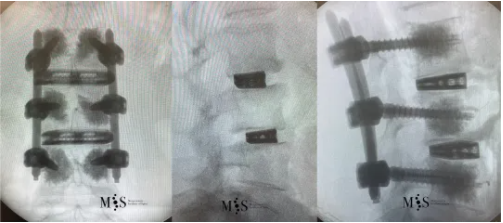

Estas imágenes muestran a una paciente con una escoliosis degenerativa lumbar (imagen del centro) y un inestabilidad en los niveles L2/L3 y L3/L4 (obsérvese un escalón en las vértebras de las imágenes izquierda y derecha) que requiere de fusión oblícua para una óptima corrección de la patología descrita.

Estas imágenes muestran la corrección post-operatoria mediante fusión oblicua-lateral (OLIF) del caso anteriormente mostrado. Obsérvese la corrección de la escoliosis en el plano frontal (imagen izquierda) y de la inestabilidad en el perfil (imagen de la derecha) con cajas de superficie amplia. La paciente ya estaba caminando a las pocas horas después de la cirugía y se le dio el alta hospitalaria a las 24 horas (ver video más abajo).